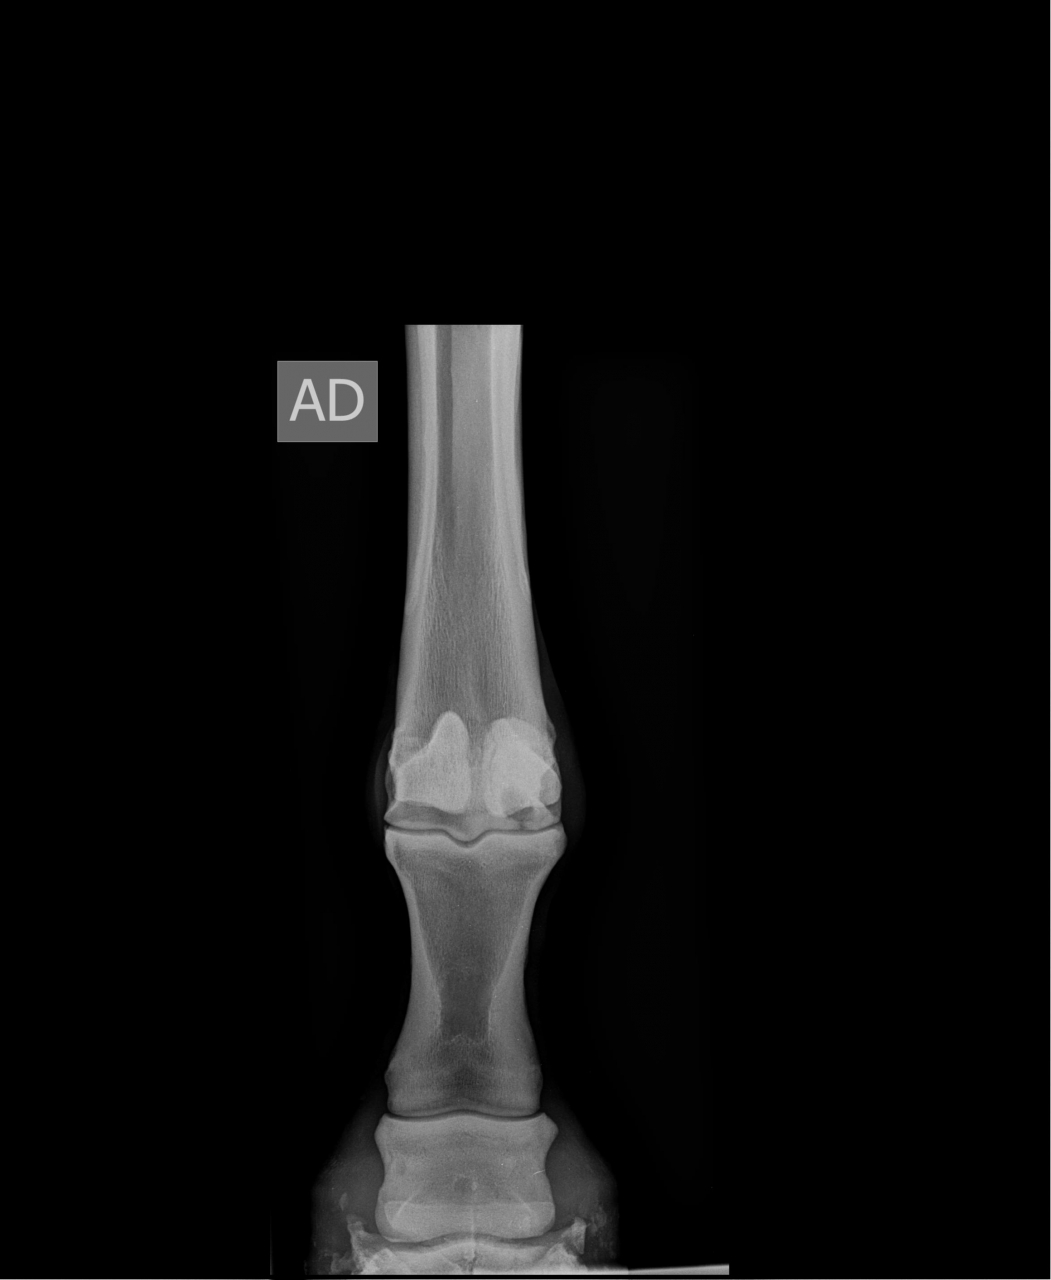

DéconnectéDire merci | Merci de vos réponses. Voici la radio de son boulet droit (le pire). Y'aurait un début d'arthrose aussi. Vous dites que la majorité retourne au sport, c'est plutôt encourageant. Est-ce sur des chevaux qui boitent déjà ? ou plutôt sur des chevaux sur lesquels on a détecté les kystes avant qu'ils soient symptomatiques ? Qu'est-ce qui va être décisif pour décider des chances de réussite de l'opération ? ![]() Je suis prète à tenter mais à condition qu'il y ait effectivement une chance que ça fonctionne, même si c'est pas du 100%. Ice queen, je suis désolée de l'issue pour votre cheval. Quelle opération a-t-elle subi ? La pose d'une vis ? |